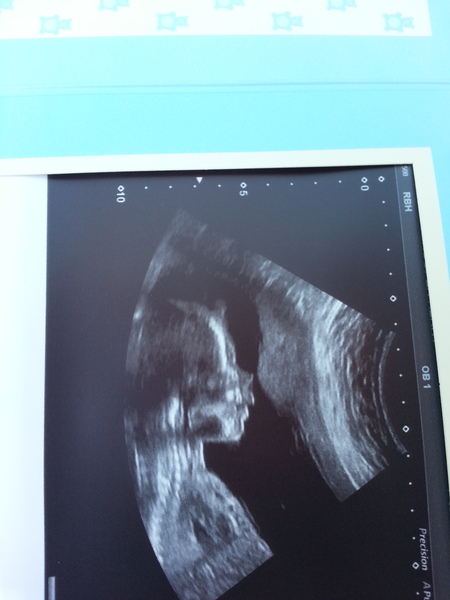

Hello from sunny Lanazrote, ladies! Grin Scan picture lovely Popcorn, have attached ours too hopefully. Dire flight as I have managed to catch a horrible cold and was hell on my sinuses but nice to be here and not have to do anything! Bit of stretchy pain today but better than it has been. Hope it improves for you amylou, hang in there!

November 2014- Thread 6- Pink, blue or yellow? 20 week scans coming up for the rainbow collective

Gorgeous scan pics, Popcorn and Twiglet - so clear. Mine were just total fuzz, I'm amazed they could decipher anything!